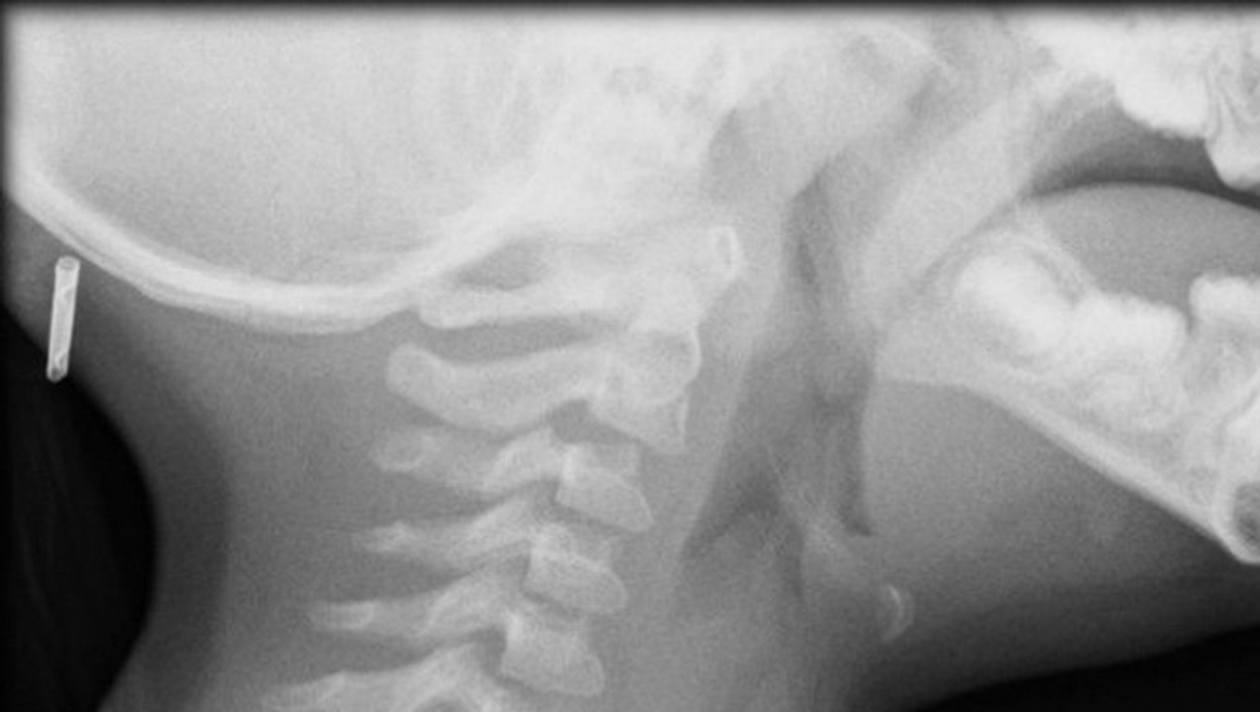

Un baiat din China s-a dus la medic, din cauza ca ragusise, tusea si deseori avea stari de voma. Cand i-au facut o radiografie, doctoral a fost ingrozit sa vada ce avea tanarul in gat.

Desi credeau ca tanarul este racit, medicii i-au facut totusi o radiografie.

Atunci au observat ca baiatul avea in gat o lipitoare, scrie Kanal D.

Lipitoarea traia acolo de mai multa vreme, cred doctorii, care in cele din urma au reusit sa indeparteze parazitul.